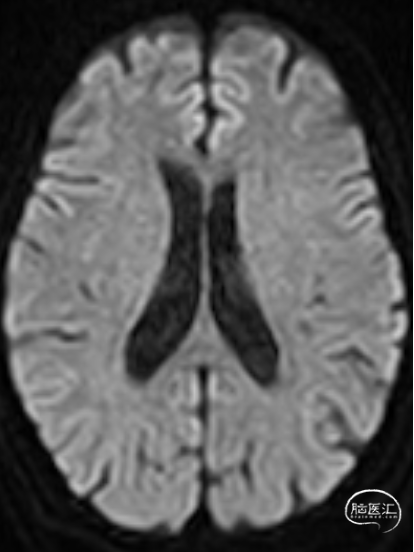

术前影像资料